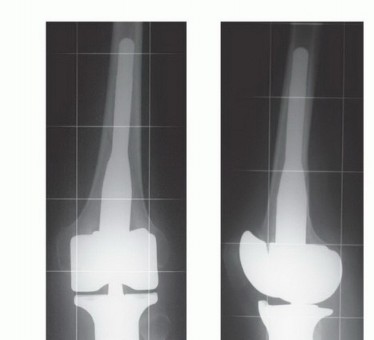

صورة توضيحية لورم في قصبة الساق القريبة.

صورة شعاعية تظهر ساركوما عظمية في قصبة الساق القريبة لمريضة تبلغ من العمر 17 عاماً.

صورة شعاعية توضح ورماً عظمياً في قصبة الساق القريبة.

صورة شعاعية تظهر ورماً خلوياً عملاقاً في قصبة الساق القريبة.

صورة شعاعية جانبية توضح ساركوما عظمية في قصبة الساق القريبة.

صورة شعاعية تظهر تدميراً قشرياً وامتداداً للأنسجة الرخوة للورم.